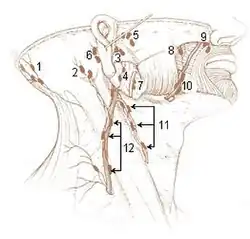

Mandibular lymph node

The mandibular lymph node is a lymph node found near the jaw.